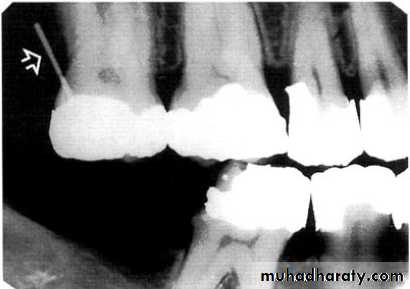

A-Calculus:

It is a stone-like concretion that forms on the crown & roots of the teeth due to the calcification of bacterial plaque.

Its appear as radiopaque on the dental radiograph.

its either pointed or irregular radiopaque projection extending from the proximal root surface.

Calculus may be seen as a ring-like radiopacity encircling the cervical portion of the tooth.